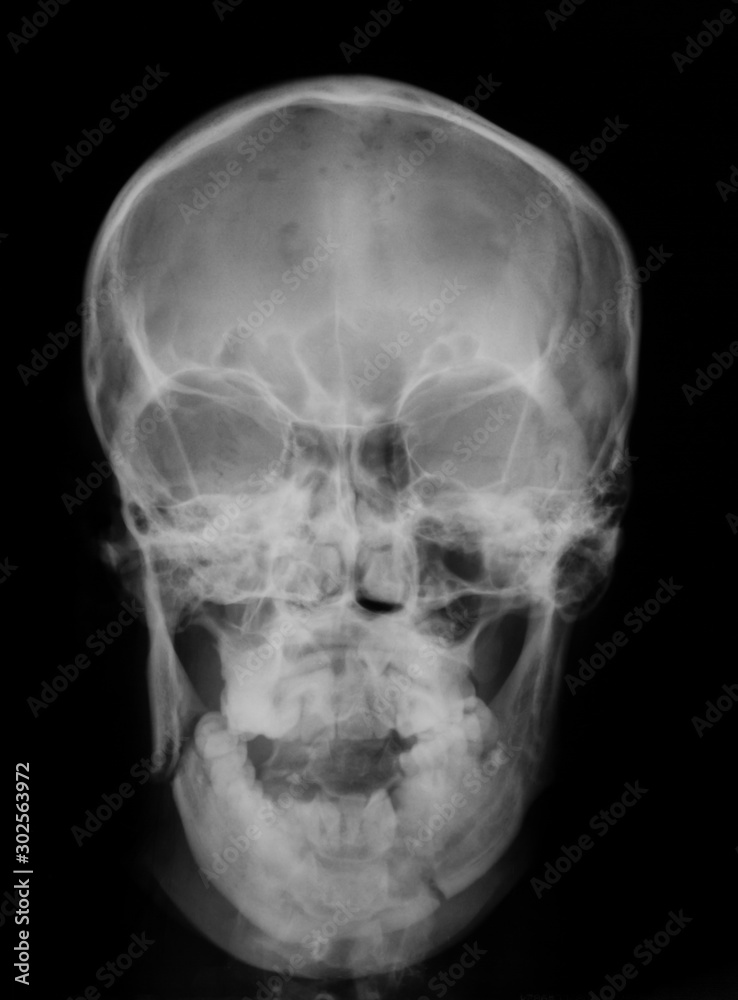

Skull xray showing bilateral maxillary sinus fractures Stock Photo Alamy Maxilla Fracture X Ray View Axial ct demonstrates (a) ethmoidal grooves within the nasal bones (arrows), which are sometimes mistaken for fractures; Helical ct and, more recently, multidetector ct. Maxillary fractures are common in patients sustaining facial trauma and may be caused by road traffic accidents, sports, or. (b) frontal processes of the maxilla. Maxillary fractures are common injuries involving the upper jaw, often requiring. Maxilla Fracture X Ray View.